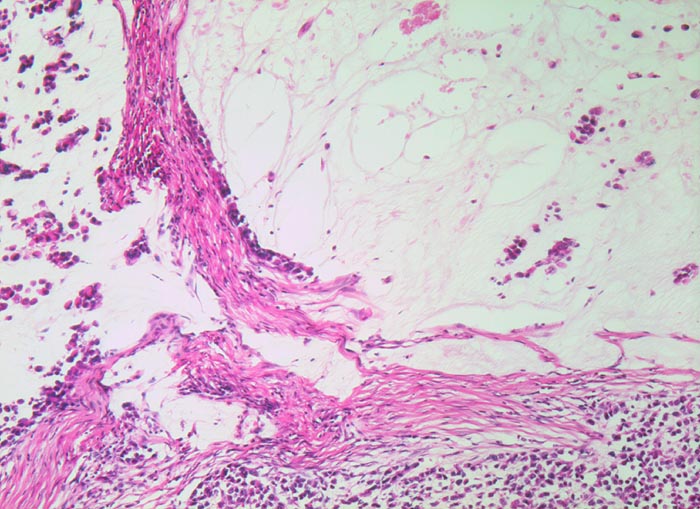

• Am unteren Ende des Präparates Antrummukosa mit mässiggradiger chronischer, geringgradig aktiver Gastritis und ausgedehnter intestinaler Metaplasie (Becherzellen).

• Weiter oben Invasion der Magenschleimhaut durch ein teils solides, teils drüsenbildendes Adenokarzinom mit stark atypischen Tumorzellen.

• Fokale Erosion des Karzinoms bedeckt von fibrinoleukozytärer Membran.

• Tumorinfiltration der Submukosa an der oberen Präparathälfte.

• Der invasive Karzinomanteil zeigt teilweise muzinöse Differenzierung (teils siegelringzellige Tumorzellen schwimmen in extrazellulären Schleimseen).

• Tumorfreie Lamina muscularis propria.